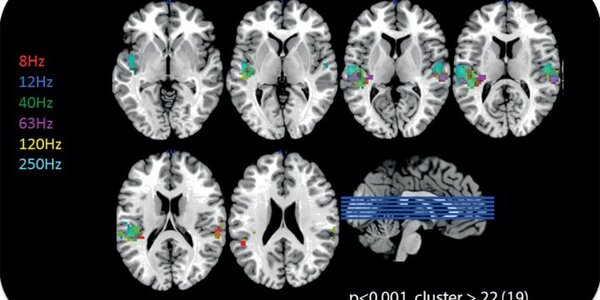

Wind Farms: Can You Actually Hear Inaudible Sound?

Are wind farms harmful to humans? Some believe so, others refute this; this controversial topic makes emotions run high. To give the debate more objectivity, an international team of experts dealt with the fundamentals of hearing in the lower limit range of the audible frequency range (i.e. infrasound), but also in the upper limit range (i.e. ultrasound). The project, which is part of the European Metrology Research Programme (EMRP), was coordinated by the Physikalisch-Technische Bundesanstalt (PTB). At PTB, not only acoustics experts, but also experts from the fields of biomagnetism (MEG)…